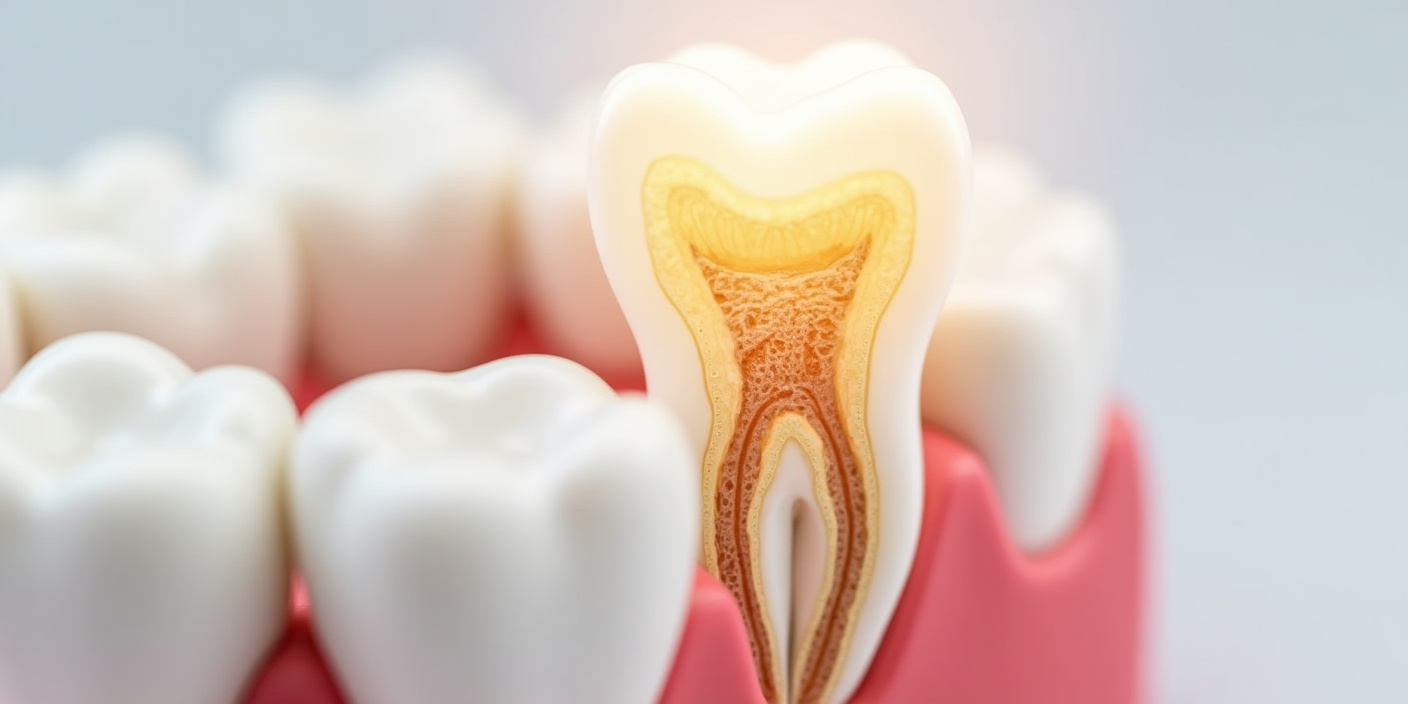

Лечение корневых каналов часто необходимо, когда зуб имеет глубокий кариес, трещину, скол или травму.